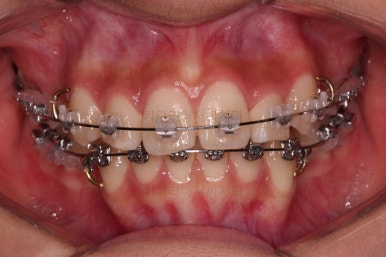

교정시작 3개월째입니다.

비발치로 가지런하게만 목표로 한다면 거의 다 끝나가네요. 효율적인 메카닉스와 술식으로 치료과정을 매우 빠르게 진행했어요.

당연히 부작용이 없는 범주 안에서 말이죠.

지금쯤 다시 발치와 비발치에 대해서 말씀을 나눕니다.

각각의 장단점, 목표로 하는 바 등을 말씀 나누고 현재의 입매에서 옆라이니 좀 더 스트레이트하게 떨어지는 라인을 원하셔서 발치교정으로 넘어가기로 결정했습니다.